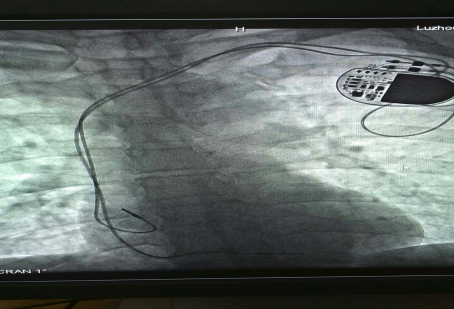

已安裝好的磁共振兼容起搏電極

近年來,隨著醫(yī)學(xué)科技的進(jìn)步帶動(dòng)了起搏器的一次次革新,磁共振檢查“大門”已經(jīng)向起搏器患者開放,可以說全面“解禁”磁共振檢查的時(shí)代到來了。通過對(duì)材料和工藝在內(nèi)的一系列技術(shù)改進(jìn),有了可以兼容的磁共振起搏系統(tǒng),包括磁共振兼容脈沖發(fā)生器和磁共振兼容起搏電極。

?“磁共振兼容起搏系統(tǒng)適用于所有起搏器植入術(shù)患者。雖然現(xiàn)在磁共振兼容性起搏器已經(jīng)用于臨床,但是由于整套系統(tǒng)的昂貴價(jià)格及醫(yī)保支付等原因,一部分患者因?yàn)榻?jīng)濟(jì)原因暫時(shí)不能植入磁共振兼容全套系統(tǒng)?!敝毂蜥t(yī)師表示,心臟起搏器系統(tǒng)包含脈沖發(fā)生器和起搏電極兩部分,起搏電極的拔除和更換手術(shù)較復(fù)雜并且具有一定的風(fēng)險(xiǎn),而單純的脈沖發(fā)生器更換術(shù)則比較簡(jiǎn)單。因此,對(duì)暫時(shí)不能植入磁共振兼容全套系統(tǒng)的患者,可以先植入磁共振兼容起搏電極導(dǎo)線,等到將來各方面條件成熟或需要做磁共振檢查時(shí)再直接更換脈沖發(fā)生器。此種方案可以滿足未來患者接受磁共振檢查的潛在需求。